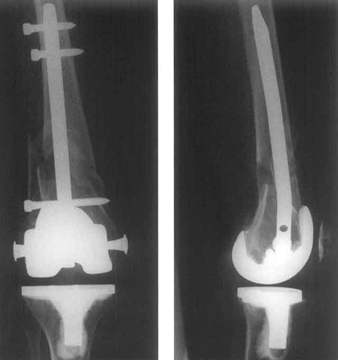

supracondyläre Fraktur bei liegender Knie TEP, Nagelung geschlossen durch das Knie

Nach oben war der Markraum mit einem Gamma-Nagel verschlossen.

Trümmerfraktur oberhalb einer liegenden KnieTEP bei ausgeprägter Osteoporose.